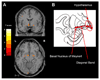

Main outcome measure: Patterns of gray matter loss in the MCI groups compared with control subjects, assessed using voxel-based morphometry.

Results: Subjects in the amnestic single- and multiple-domain groups showed loss in the medial and inferior temporal lobes compared with control subjects, and those in the multiple-domain group also had involvement of the posterior temporal lobe, parietal association cortex, and posterior cingulate. Subjects in the nonamnestic single-domain group with language impairment showed loss in the left anterior inferior temporal lobe. The group with attention/executive deficits showed loss in the basal forebrain and hypothalamus. No coherent patterns of loss were observed in the other subgroups.